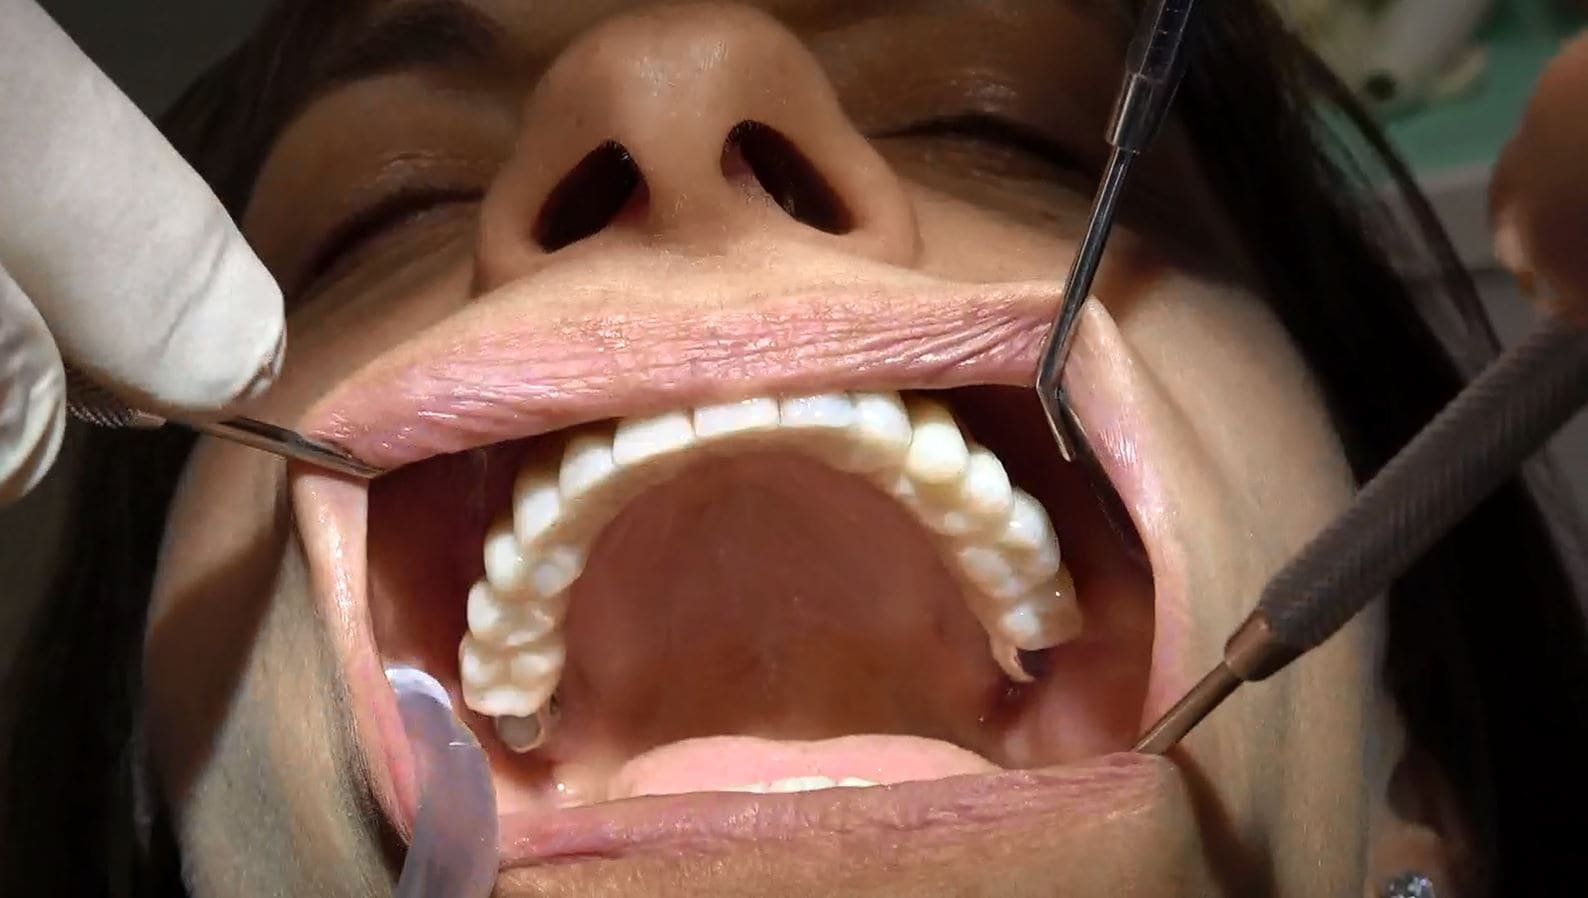

• Il video documenta ogni fase dell’intervento, dalla progettazione personalizzata della griglia sottoperiostea all’applicazione dei singoli impianti e, infine, alla realizzazione di una protesi dentale a carico immediato.

• Accompagniamo il video con una galleria fotografica dettagliata che cattura ogni fase del processo e i risultati finali sorprendenti.

• Una delle caratteristiche distintive di questa tecnica è il carico immediato. Subito dopo l’inserimento della griglia e degli impianti, viene applicata una protesi dentale fissa provvisoria, consentendoti di avere denti fissi fin dalla stessa giornata dell’intervento.

PAZIENTE PASSA DA 30 ANNI DI DENTIERA A DENTI FISSI PROVVISORI POI DEFINITIVI NEL GIRO DI UN ORA E TRENTA MINUTI